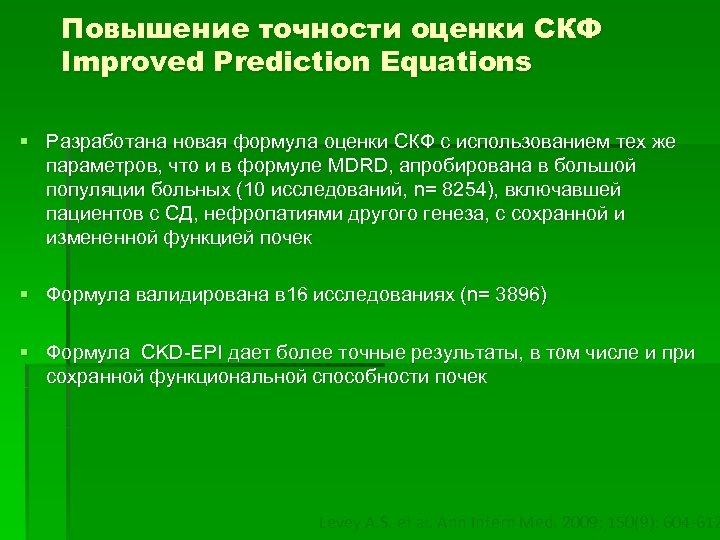

Повышение точности оценки СКФ Improved Prediction Equations § Разработана новая формула оценки СКФ с использованием тех же параметров, что и в формуле MDRD, апробирована в большой популяции больных (10 исследований, n= 8254), включавшей пациентов с СД, нефропатиями другого генеза, с сохранной и измененной функцией почек § Формула валидирована в 16 исследованиях (n= 3896) § Формула CKD-EPI дает более точные результаты, в том числе и при сохранной функциональной способности почек Levey A. S. et al. Ann Intern Med. 2009; 150(9): 604 -612